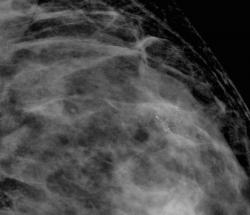

привожу случай снова.В верхне-наружном квадранте левой молочной железы отмечаются сгруппированные микарокальцианты без явной принадлежнсти к узловому образованию

Пациентка прооперирована. Гистология по cito: инфильтрирующий рак с участками слизистого рака.

Спасибо за случай. По большому счету, конечно, кое, что исчезло. Но большинство иллюстрации наших пользователей продублировано и никуда не делось. Имею вопрос. Рак ьыл обнаружженов зоне микрокальцинатов или нет?